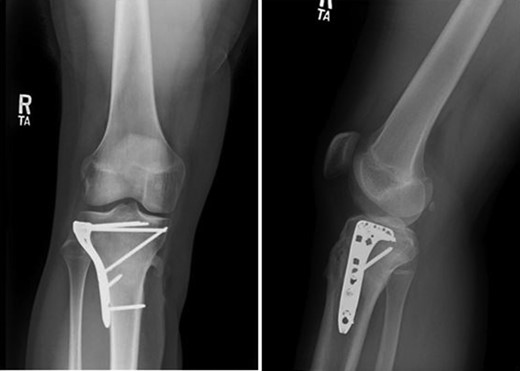

Patient is a 14-year-old male who slipped and fell while jumping off of a diving board and landed onto a flexed right knee. The patient was stable on presentation and neurovascularly intact with the knee locked in flexion. Skin was tenting anteriorly over the tibial tubercle and his compartments were swollen but compressible. A single plain film view (Fig. 1) was obtained prior to orthopaedic consultation. Closed reduction under sedation and splitting was attempted in the ED with partial but unsatisfactory improvement. Post-reduction radiographs (Fig. 2) demonstrated a tibial tubercle fracture with extension through the entire proximal tibial physis with metaphyseal involvement posteromedially. We classified this as a type IV tibial tubercle fracture, Salter–Harris II variant. In conjunction with patient and family we planned for urgent closed versus open reduction and application of knee-spanning external fixator. Immediately prior to surgery in the pre-operative holding area, the patient noted increasing right leg pain. In the operating room (OR), a marked increase in swelling with tense skin was observed. Due to rapidly progressive swelling and nature of the fracture, the decision was made to proceed with a 4-compartment fasciotomy of the right leg. The medial-sided fasciotomy (Fig. 3) revealed significant bulging of the superficial and deep compartments; however, the anterior and lateral compartments were less swollen. The fracture was unable to be closed reduced intraoperatively, therefore proximal extension of the medial fasciotomy wound was performed to open and reduce the fracture under direct visualization. Anatomic reduction was achieved and a knee-spanning external fixator was applied (Fig. 4). Approximately 72 hours later the patient was brought back to the OR for irrigation and debridement, lateral wound closure, and medial wound vacuum placement. Another 72 hours later, he returned to the OR for removal of the external fixator, ORIF, and split-thickness skin grafting of the medial fasciotomy site. An anterolateral approach was used with a 3.5 mm proximal tibial locking plate (Fig. 5). At most recent follow-up (Fig. 6), six months post-op, the patient is pain free, ambulating without assistive device, and has returned to all desired activities.

AP and lateral radiographs after attempted closed reduction which reveal type IV tibial tubercle fracture with posteromedial metaphyseal extension (Salter–Harris II variant).

AP and lateral radiographs following open reduction and application of knee-spanning external fixator.